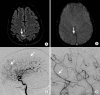

Intracranial hemorrhage is common and is caused by diverse pathology, including trauma, hypertension, cerebral amyloid angiopathy, hemorrhagic conversion of ischemic infarction, cerebral aneurysms, cerebral arteriovenous malformations, dural arteriovenous fistula, vasculitis, and venous sinus thrombosis, among other causes. Neuroimaging is essential for the treating physician to identify the cause of hemorrhage and to understand the location and severity of hemorrhage, the risk of impending cerebral injury, and to guide often emergent patient treatment. We review CT and MRI evaluation of intracranial hemorrhage with the goal of providing a broad overview of the diverse causes and varied appearances of intracranial hemorrhage.